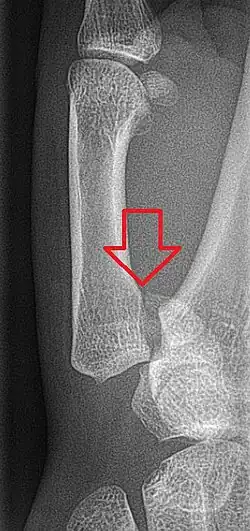

In the case of the Bennett fracture, the proximal metacarpal fragment remains attached to the anterior oblique ligament, which in turn is attached to the tubercle of the trapezium bone of the CMC joint. This ligamentous attachment ensures that the proximal fragment remains in its correct anatomical position.

The distal fragment of the first metacarpal bone possesses the majority of the articular surface of the first CMC joint. Unlike the proximal fracture fragment, strong ligaments and muscle tendons of the hand tend to pull this fragment out of its correct anatomical position.

Specifically:

- tension from the abductor pollicis longus muscle (APL) subluxates the fragment in a dorsal, radial, and proximal direction

- tension from the APL rotates the fragment into supination

- tension from the adductor pollicis muscle (ADP) displaces the metacarpal head into the palm

Tension from the APL and ADP muscles frequently leads to displacement of the fracture fragments, even in cases where the fracture fragments are initially in their proper anatomic position. Because of the aforementioned biomechanical features, Bennett fractures nearly always require some form of intervention to ensure healing in the correct anatomical position and restoration of proper function of the thumb CMC joint.